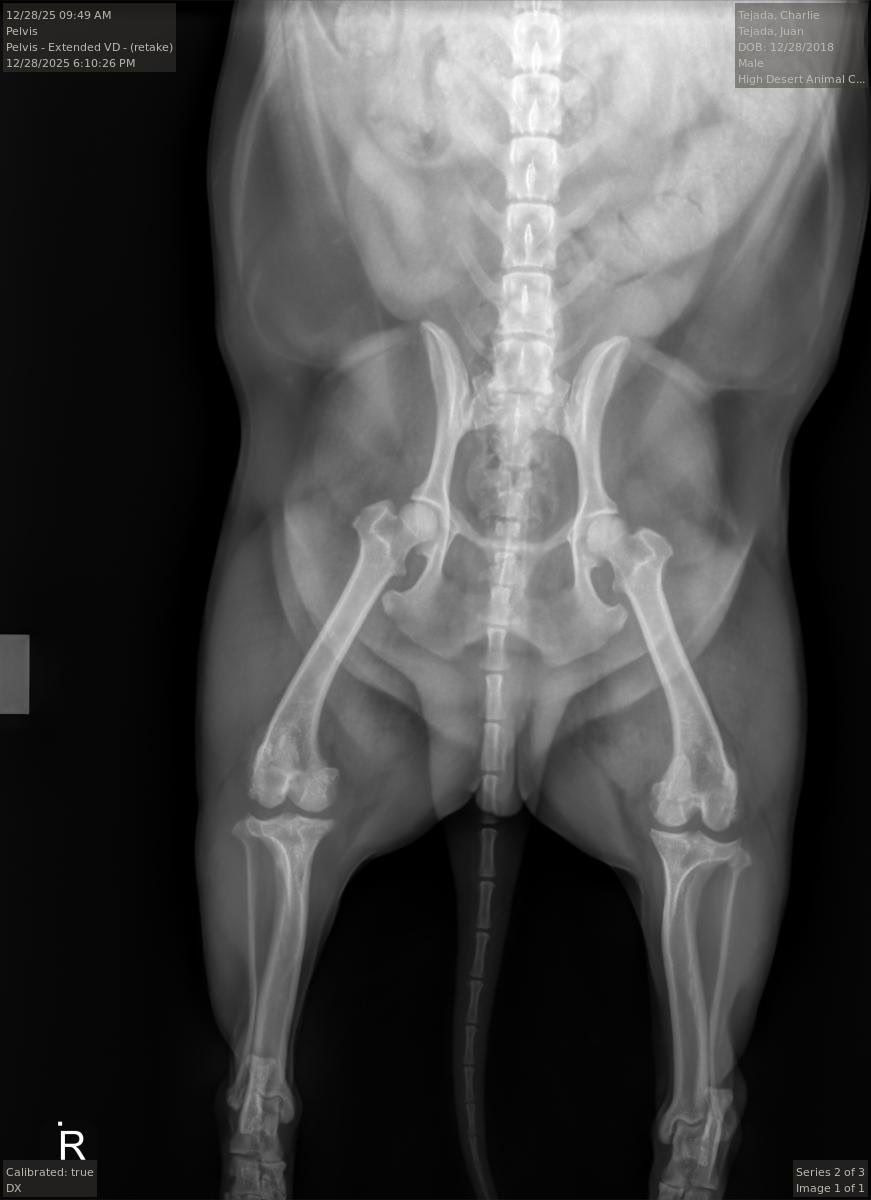

Charlie is my mother’s beloved dog, and he truly means the world to her. Recently, Charlie had a terrible accident—he jumped out of the car and tore his meniscus. Since then, he’s been in a lot of pain, and it’s been heartbreaking for my mom to see him struggle. Charlie has always been a source of comfort and joy for her, and seeing him hurt has been incredibly difficult for our whole family.

The veterinarian has recommended surgery to put a plate and screw in Charlie’s leg so he can recover and live pain-free. The cost of the procedure is overwhelming for my mom, and she’s devastated by the thought of not being able to help her best friend. She doesn’t want to put Charlie down or let him continue to suffer, but the financial burden is just too much for her to handle alone.

The veterinarian has recommended surgery to put a plate and screw in Charlie’s leg so he can recover and live pain-free. The cost of the procedure is overwhelming for my mom, and she’s devastated by the thought of not being able to help her best friend. She doesn’t want to put Charlie down or let him continue to suffer, but the financial burden is just too much for her to handle alone.